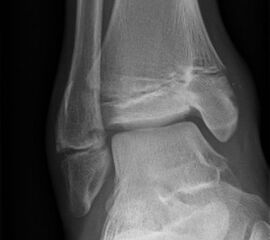

Fugengelenkfrakturen treten typischerweise vor dem 10. Lebensjahr auf, in einer Phase, in welcher die Wachstumsfugen noch weit offen sind. Dieser Frakturtyp betrifft fast ausschließlich den medialen Malleolus. Laterale Frakturen sind extrem selten, teilweise kommt es zu lateralen Bandverletzungen oder Fugenschaftfrakturen der distalen Fibula. Die Frakturlinie verläuft in einer Verlängerungslinie von der medialen Taluskante nach proximal. Häufig stellen sich Verletzungen des Innenknöchels im Röntgenbild schlechter dar, insbesondere wenn die Aufnahmen verdreht sind oder die Ebene der Fraktur bei geringer Dislokation verkippt zur Röntgenebene liegt. Besteht klinisch der geringste Hinweis auf eine Verletzung des Innenknöchels, muss aufgrund der Tragweite der Verletzung durch entsprechende Aufnahmen gegebenenfalls auch Schnittbildverfahren die Verletzung sicher diagnostiziert oder ausgeschlossen werden (Abb. 15).

„Kadiläsion“- Mediale Malleolarfraktur

Bei kindlichen Verletzungen des medialen Malleolus handelt es sich nach L. v. Laer um eine sogenannte Kadiläsion, d.h. eine Verletzung mit hohem Risiko eines schlechten Behandlungsergebnisses bei nicht korrekter Behandlung. Selbst bei optimaler Therapie ist das Risiko für spätere Wachstumsstörungen hoch, sodass diese Verletzungen nicht selten ein juristisches Nachspiel haben. Durch die Verletzung der wachstumsaktiven Zone kann es zu einem vorzeitigen Verschluss der Wachstumsfuge kommen, mit entsprechendem Fehlwachstum. Das Risiko eines vorzeitigen Verschlusses der Wachstumsfuge korreliert mit dem Ausmaß der Schädigung der wachstumsaktiven Zone. Ab dem 13. Lebensjahr wird das Risiko bei reduzierter Wachstumsaktivität zunehmend geringer.

Fugengelenkfrakturen können die Wachstumsfuge durchkreuzen (Abbildung 16a), ohne oder nur mit minimaler Beteiligung der Fuge sehr weit medial liegen (Abbildung 16b) oder durch die Fuge auslaufen (Abbildung 16c). Relevant für die Wachstumsprognose ist weniger die Form der Fraktur, sondern das Alter des Patienten zum Zeitpunkt des Traumas sowie das Ausmaß der Schädigung der Wachstumsfuge, wobei eine Korrelation mit dem Ausmaß der Dislokation besteht.